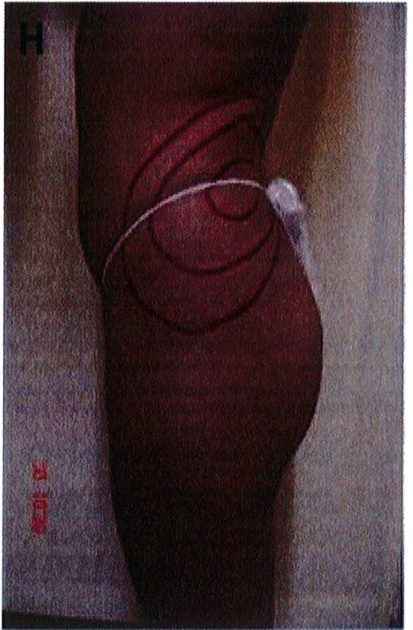

Hình. 3. (A-H) Tiền phẫu, chu phẫu và sau hậu phẫu 6 tháng của một bệnh nhân nữ 38 tuổi đươc ghép túi đôn mông với thể tích 330 cm3.

Hình. 4. (A-I) Hình ảnh tiền phẫu, chu phẫu và sau hậu phẫu 11 tháng của một phụ nữ 25 tuổi đã được thực hiện hút mỡ vùng éo, hông và sau xương vùng, đồng thời ghép khối cấy thể tích 270cm3.